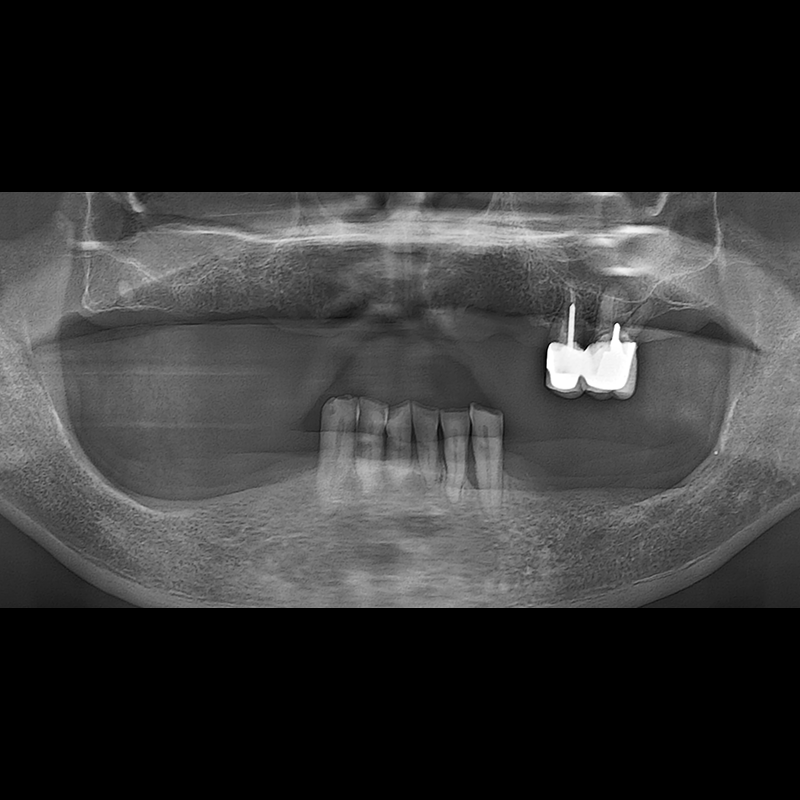

BEFORE AFTER

种植牙前后的照片 2025.05.30

在缺失的牙齿部分和难以挽救的牙齿位置植入了种植牙。